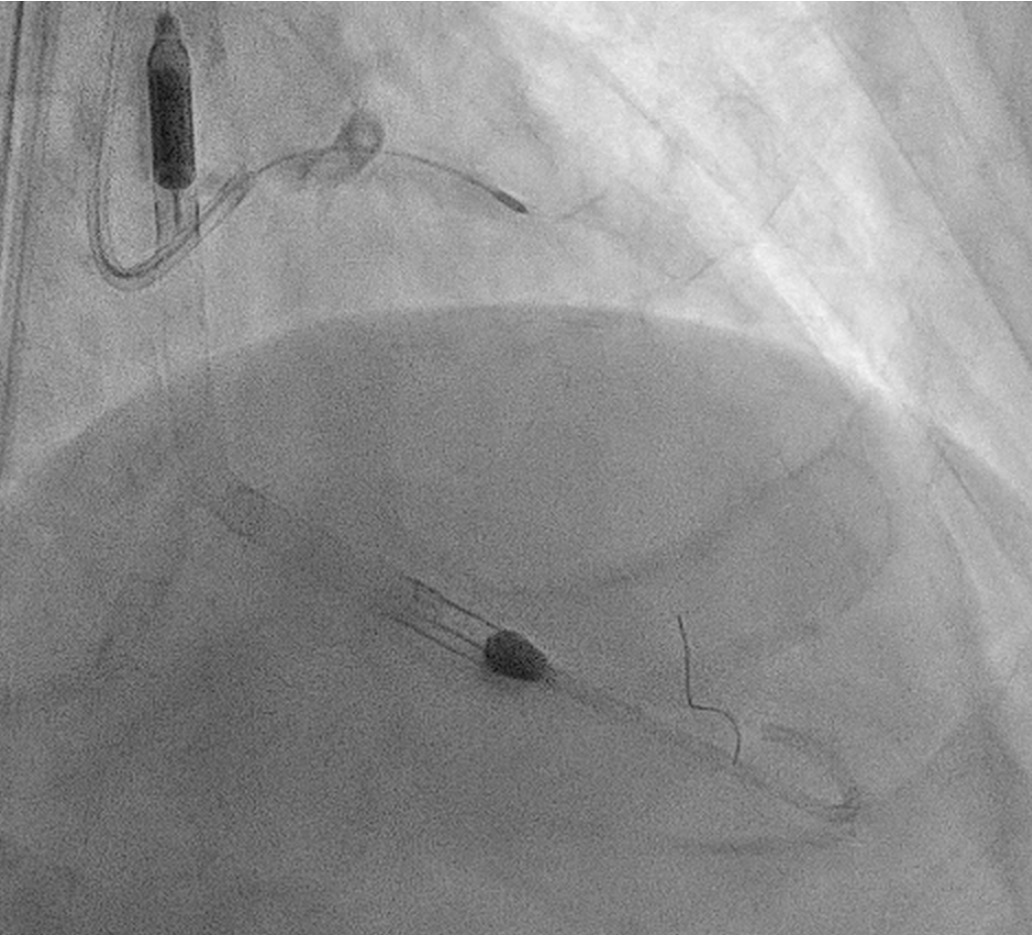

The Vascular team performed aortoiliac revascularisation to concurrently treat his peripheral vascular disease and allow for femoral access for CHIP. Kissing covered stents were placed from the abdominal aorta to bilateral CIAs and EIAs using the ¡°pave and crack¡± technique with chimney stenting to the IMA. After recovery, single access for Impella CP supported high-risk PCI (SHiP) was performed via the left femoral artery with a 7F sheath through the 14F Impella sheath. Intervention began with the LAD using rotational atherectomy (1.25mm burr) but led to hemodynamic instability despite Impella support, requiring emergency intubation and dopamine infusion. Significant blood loss was noted from the SHiP access due to the inadvertent migration of the PCI sheath proximally, and addressed by repositioning the sheath and transfusion. Once stabilised, the LAD, diagonal, and LCx arteries were treated with rotational atherectomy (1.25mm burr). The LCx had follow up orbital atherectomy, and scoring balloon angioplasty for a large ostial calcific nodule. The left main stem bifurcation was treated with drug eluting stents using OCT guided nano crush technique (3.5/28mm LMS-LAD, 3.5/28mm LCx). The first diagonal and mid LCx were treated with drug eluting balloons (2.5/30mm, 2.5/20mm). Final POT was performed in the LMS (4.0/8mm non-compliant at 18atm). Final OCT and angiography showed satisfactory result with TIMI 3 flow.